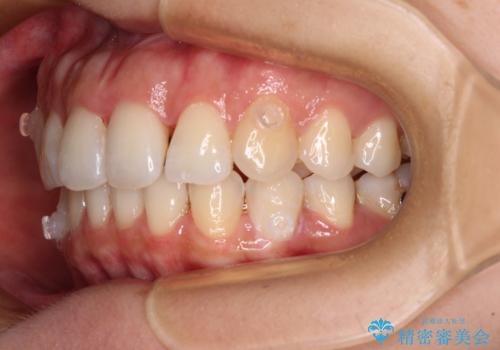

- 捻れた前歯が飛び出しており、口が閉じにくいとのことで来院された患者様です。

出っ歯というわけではないものの、前歯の捻転により口唇が押し出されている状態でした。

親知らずを抜去し、歯列全体を後方に移動させつつ、IPR(歯と歯の間を削る)でスペースを獲得し、インビザラインを用いて叢生を解消しながら前歯の突出を改善することとしました。

骨格的に上下正中がずれていたため、奥歯がしっかりと噛み合うか心配でしたが、ずれているなりに、しっかりとした咬み合わせとなりました。